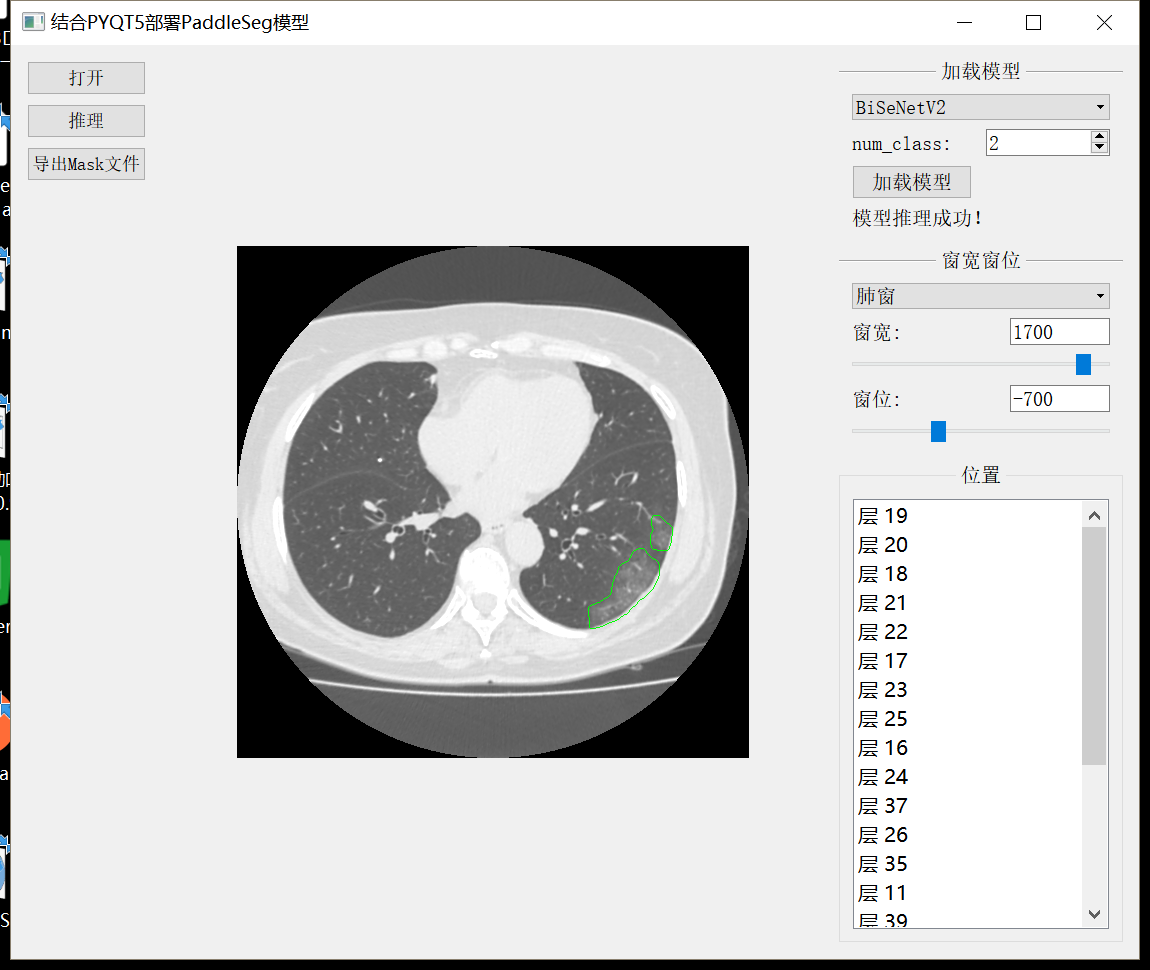

最终结果 结合PyQt制作病灶检测小工具

结合PyQT制作小工具效果如下图:

最后结合PyQT制作磨玻璃病灶检测小工具

如图

小工具的代码在项目文件游览器中,需要的可以下载试试,因为是花了一天临时写的,所以假如出现各种各样的问题,请轻喷